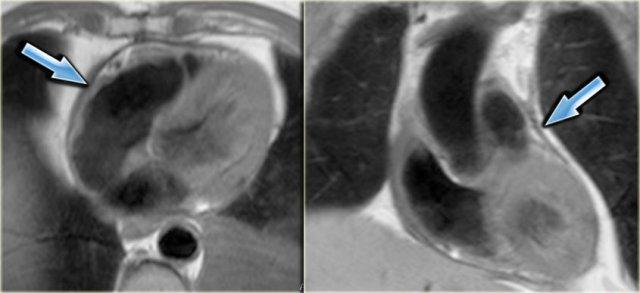

Bên trái là ảnh ngấm thuốc muộn trục dài của cùng bệnh nhân.

Lưu ý các điểm sau:

- Ngấm thuốc xuyên thành thành dưới, có thể chẩn đoán là nhồi máu cũ (mũi tên vàng)

-

Không có ngấm thuốc ở thành trước giảm vận động (mũi tên xanh).

Do đó có thể kết luận rằng đây có khả năng là kết quả của ngủ đông cơ tim.

Sau can thiệp nong mạch vành qua da (PTCA), chức năng thành trước đã cải thiện.

Phân suất tống máu cải thiện từ 17% lên 49%.